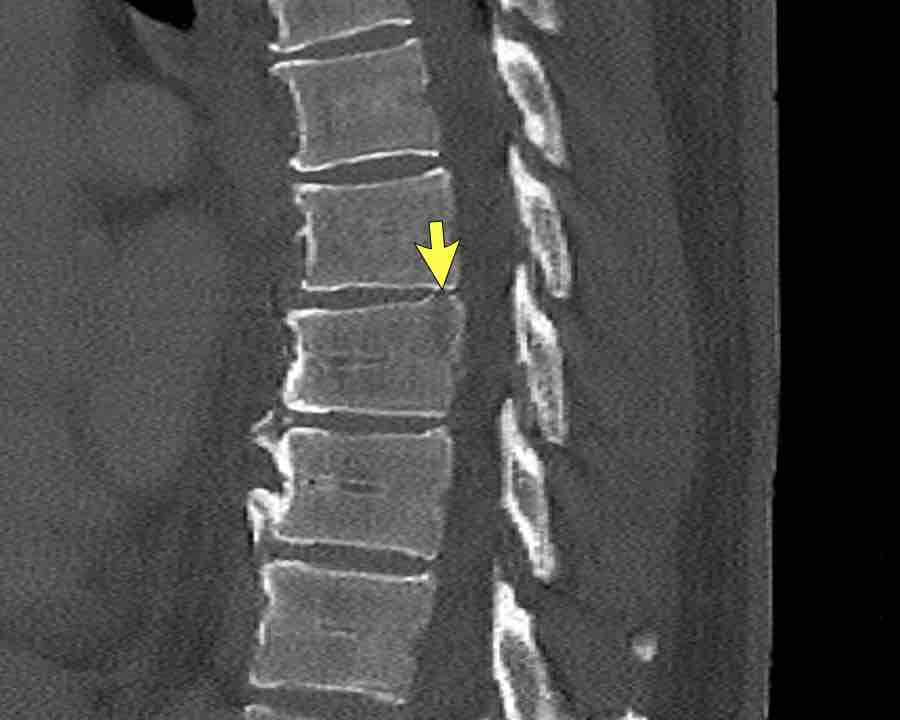

Findings

- Vertical fracture of the posterior border of the vertebral body. It looks a bit odd.

- Again we first have to look for the presence of a type C injury.

- Notice that there is a subtle posterior dislocation of the proximal levels. So this has to be C injury.

Conclusion

Injury type C + A3